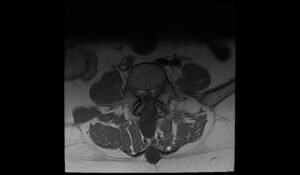

CSF leak MRI | Radiology article on CSF leak